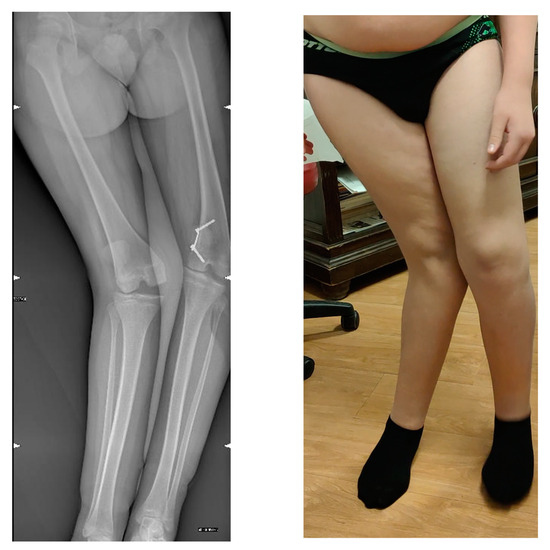

2.1. Case Presentation